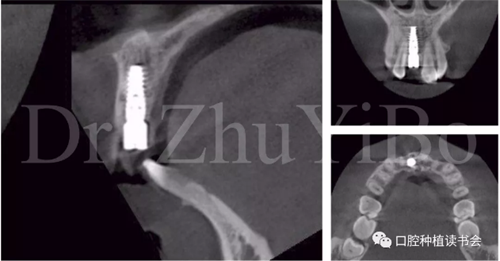

術前cbct顯示:右上中切牙牙根牙槽突類型為一型(圖8)。牙齦為厚型牙齦類型;咬合關系基本正常。

圖8 CBCT:11可見明顯根折線,無法保留

圖15術后即刻CBCT示:種植體軸向及深度良好